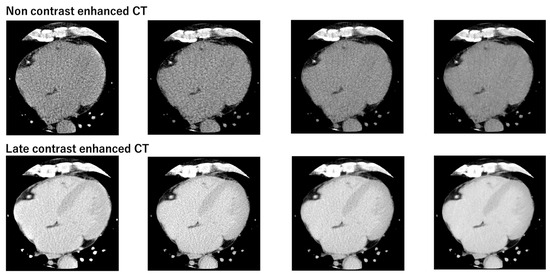

3.3. Comparison of Synthetic ECV and Laboratory ECV across Four Reconstruction Methods in the Validation Cohort